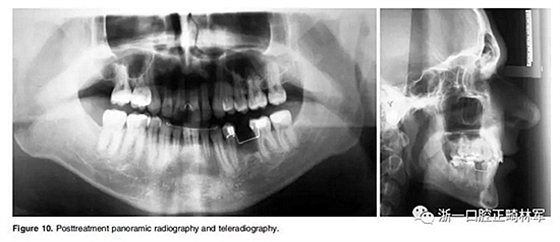

全景片顯示牙根平行度良好、無吸收。此外,在左下第二前磨牙的區(qū)域獲得了用于植入種植體修復(fù)的良好空間。頭顱側(cè)位片和疊加顯示,上下切牙傾斜度以及前后和垂直向位置的變化也很大(Figure 10、11; Table 1)。